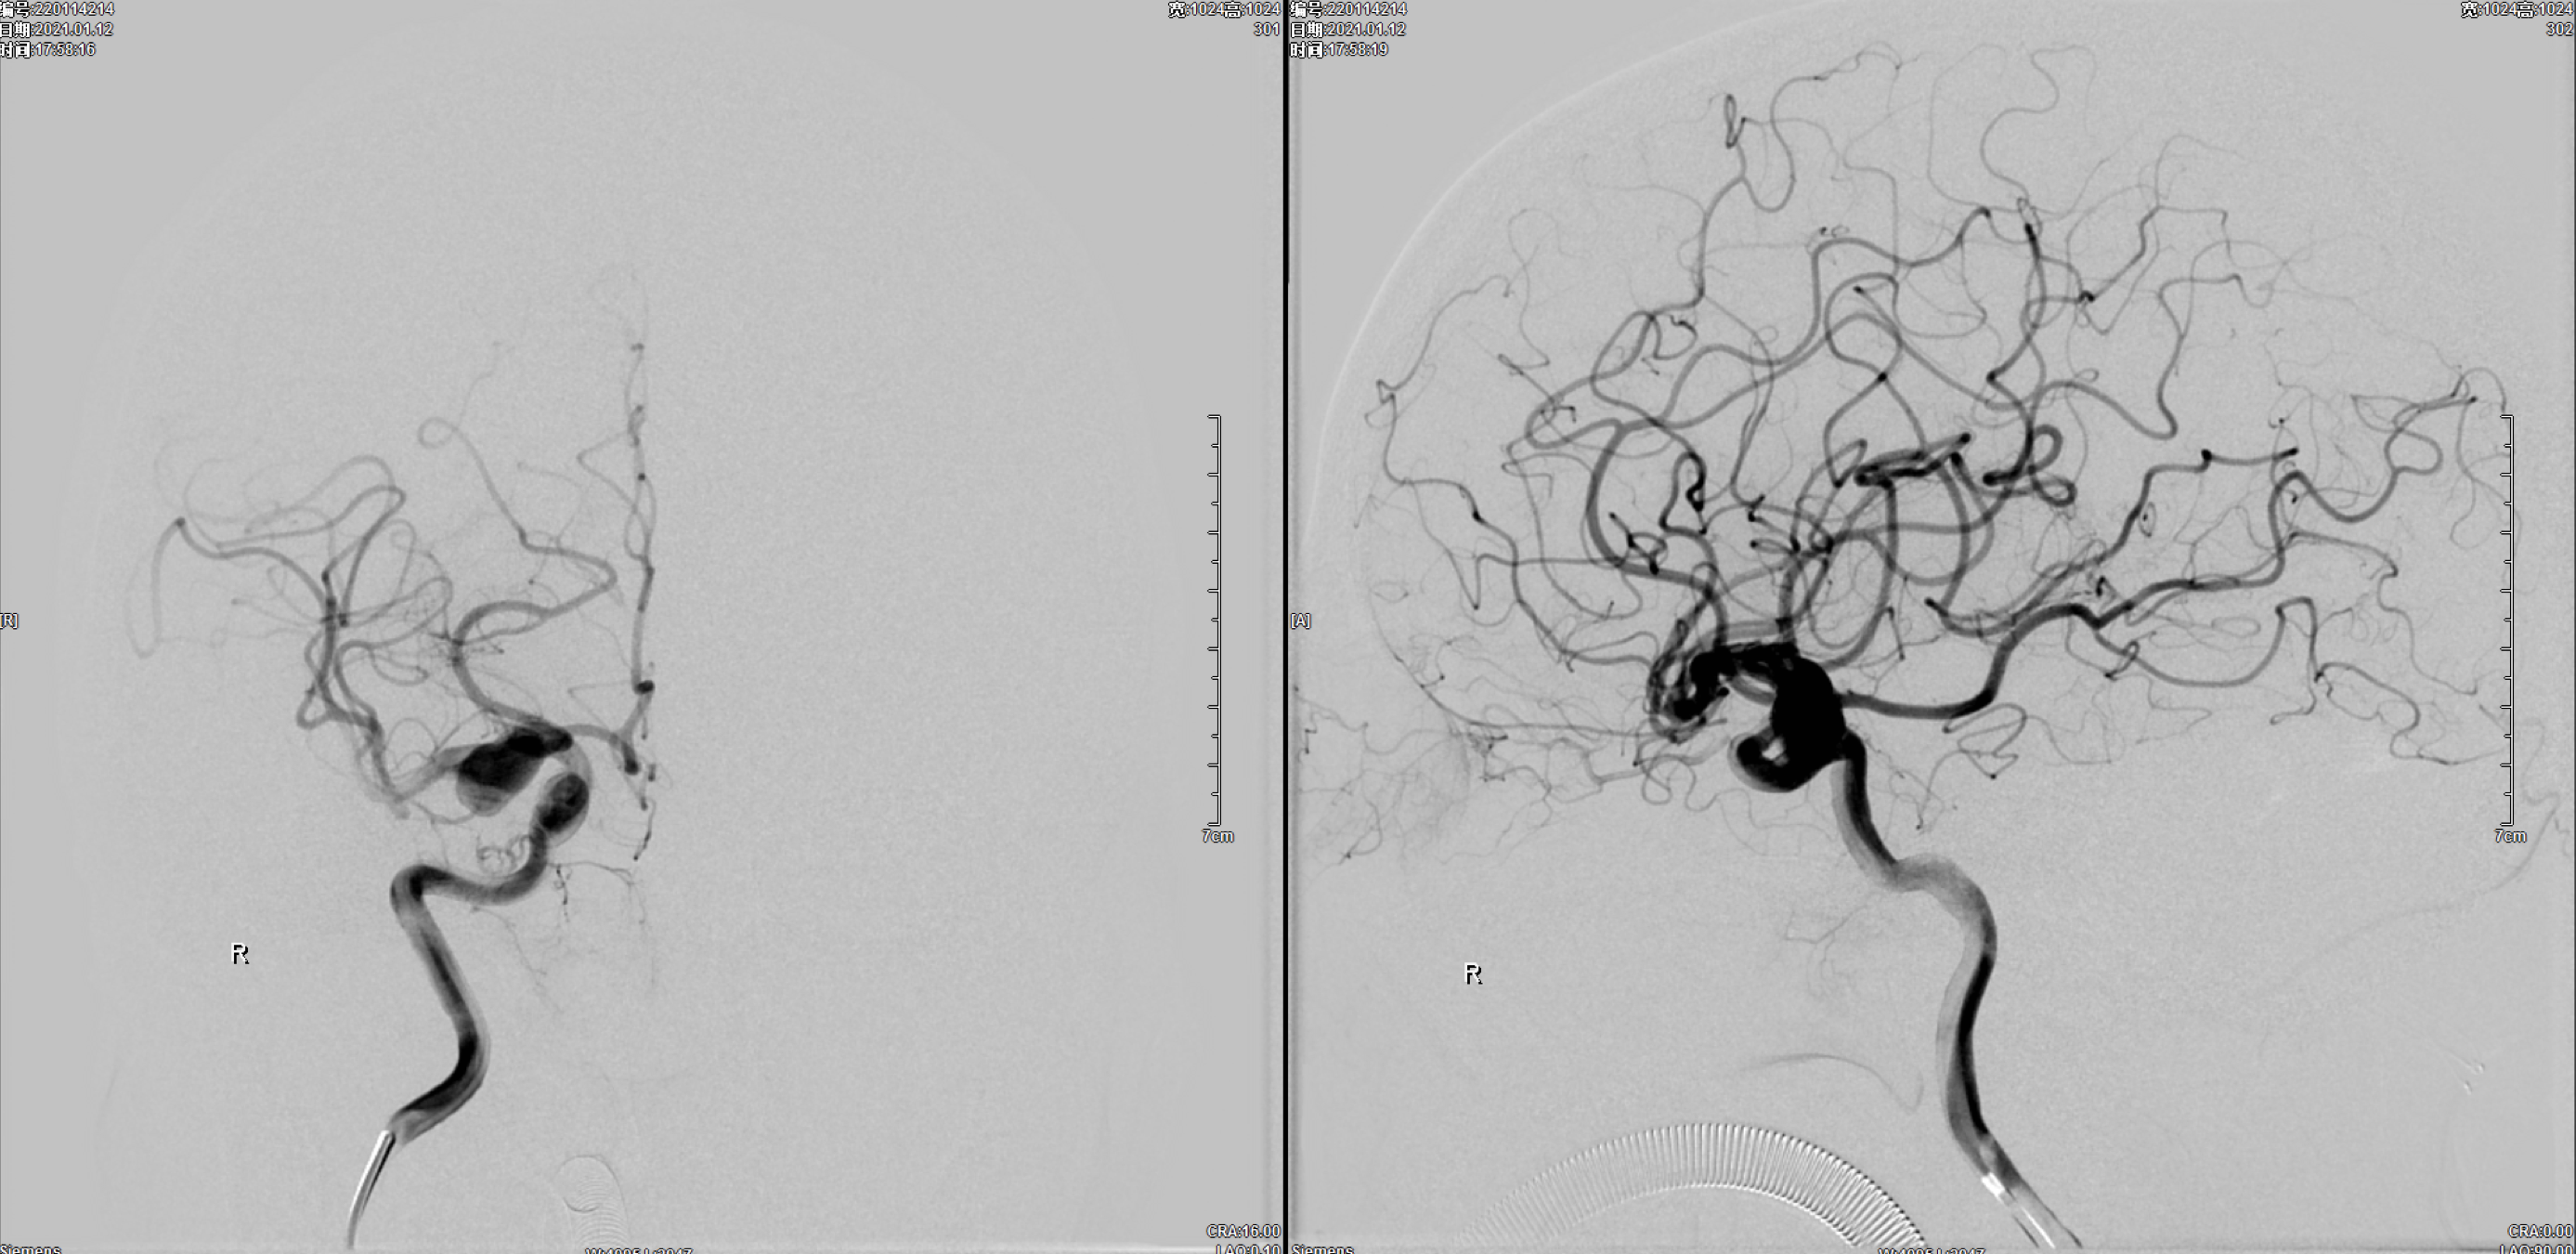

术后即刻正位造影:动脉瘤栓塞满意!

术后即刻侧位造影:动脉瘤栓塞满意!

术后三维重建:动脉瘤栓塞满意,后交通动脉保留!